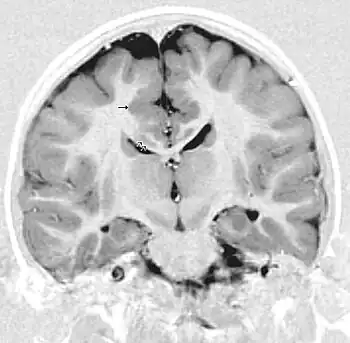

| MRI of a child experiencing seizures. There are small foci of grey matter heterotopia in the corpus callosum, deep to the dysplastic cortex. (double arrows) | |

Gray matter heterotopia is a neurological disorder caused by gray matter being located in an atypical location in the brain.[1] Grey matter heterotopia is characterized as a type of focal cortical dysplasia. The neurons in heterotopia are otherwise healthy; nuclear studies have shown glucose metabolism equal to that of normally positioned gray matter.[2] The condition causes a variety of symptoms, but usually includes some degree of epilepsy or recurring seizures, and often affects the brain's ability to function.

Detection of heterotopia generally occurs when a patient receives brain imaging—usually an MRI or CT scan—to diagnose seizures that are resistant to medication. Correct diagnosis requires a high degree of radiological skill, due to the heterotopia's resemblance to other masses in the brain.